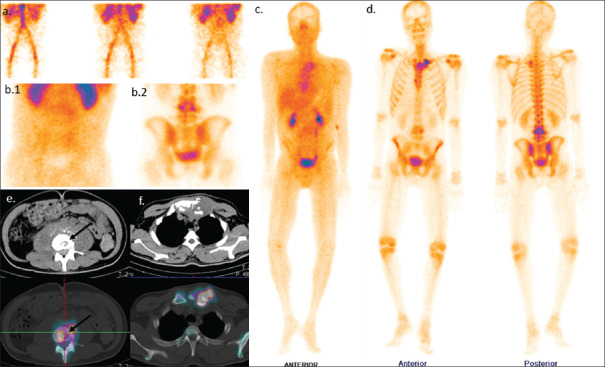

Uomo di 35 anni con lombalgia in peggioramento da 6 mesi e recente insorgenza di dolore alla spalla sinistra, associati a inappetenza e malessere. È stata eseguita una scintigrafia ossea trifasica con 99mTc-MDP.

La fase di flusso ha mostrato un’ipervascolarizzazione a livello delle vertebre L3-L4 (a). Le immagini statiche di blood-pool (b. 1) e tardive (b. 2) della regione lombare hanno evidenziato un aumentato accumulo ematico e una captazione tardiva del tracciante nella medesima regione a livello L3-L4. L’immagine whole-body di blood-pool (c) e le immagini tardive (d) acquisite dopo 3 ore hanno mostrato un’aumentata captazione a livello delle vertebre L3-L4, dell’articolazione sterno-claveare sinistra e del manubrio dello sterno. Le immagini SPECT-TC della vertebra L4 (e) hanno rivelato una lesione distruttiva con interessamento dei tessuti molli pre- e paravertebrali; reperti simili di distruzione e raccolta fluida sono stati notati nell’articolazione sterno-claveare sinistra (f). Nella lesione vertebrale si osserva un sequestro a bottone (freccia nera). La RM eseguita 2 giorni dopo ha confermato una spondilodiscite.

Donna di 47 anni con carcinoma neuroendocrino polmonare in stadiazione pre-trattamento.

L’imaging funzionale ha rilevato una chiara ipercaptazione patologica alla vertebra L5, caratterizzata da un elevato valore quantitativo (SUVmax = 45.41). Tuttavia, l’imaging morfologico (TC) iniziale era completamente negativo, non mostrando alterazioni strutturali dell’osso (C).

A distanza di tempo, l’esame TC di controllo ha documentato l’insorgenza di reazione osteoblastica (sclerosi) esattamente nello stesso punto segnalato dalla SPECT/TC mesi prima (E).

Questo caso “vero positivo” dimostra l’eccellente sensibilità dell’imaging scintigrafico (e in particolare della SPECT/TC quantitativa) nell’identificare micrometastasi o lesioni ossee in fase estremamente precoce, con largo anticipo rispetto alla comparsa dei segni morfologici visibili alla radiologia tradizionale.

Uomo di 70 anni con carcinoma adenosquamoso polmonare in stadiazione pre-trattamento.

L’imaging scintigrafico e SPECT/TC ha rilevato un’ipercaptazione focale a livello dell’osso iliaco destro (SUVmax = 15.60), corrispondente ad un’area di sclerosi ossea alla TC di natura non univoca (2,6 x 1,6 cm, densità media di 650 HU).

Nonostante la malattia di base sia andata in progressione sistemica (comparsa di metastasi al fegato e alla vertebra L1), la lesione iliaca è rimasta morfologicamente e densitometricamente stabile ad oltre un anno di distanza (dimensioni invariate, densità di 648 HU).

Questo caso “vero negativo” illustra un tipico pitfall diagnostico. La stabilità dimensionale e densitometrica (espressa in Unità Hounsfield) nel tempo conferma che l’area osteosclerotica ipercaptante non era una metastasi, ma una lesione ossea benigna (probabilmente un’isola ossea o enostosi).

Uomo con mCRPC, valutato pre- e post-terapia.

Il Bone Scan Index viene utilizzato per quantificare visivamente (in rosso) e numericamente il carico tumorale (tumor burden) a livello scheletrico, confrontando l’esame basale con quello di follow-up.

Le immagini documentano un evidente aumento delle lesioni metastatiche nel tempo. Questo si traduce in un marcato incremento del valore del BSI nonostante l’approccio terapeutico (deprivazione androgenica).

L’analisi quantitativa conferma che un “delta” (variazione) elevato del BSI in aumento è un marker sfavorevole, strettamente correlato a una prognosi peggiore e a una ridotta sopravvivenza globale.